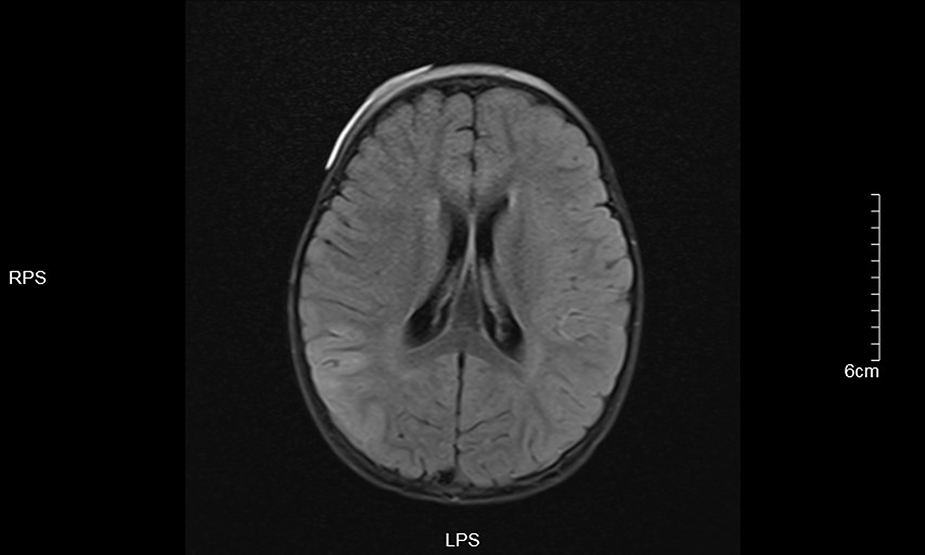

Figure 5

Left frontotemporal lobe and right temporo-occipital lobe T1 in Dark-fluid sequence slightly swollen left frontotemporal lobe and right temporo-occipital lobe gyri with increased signals.